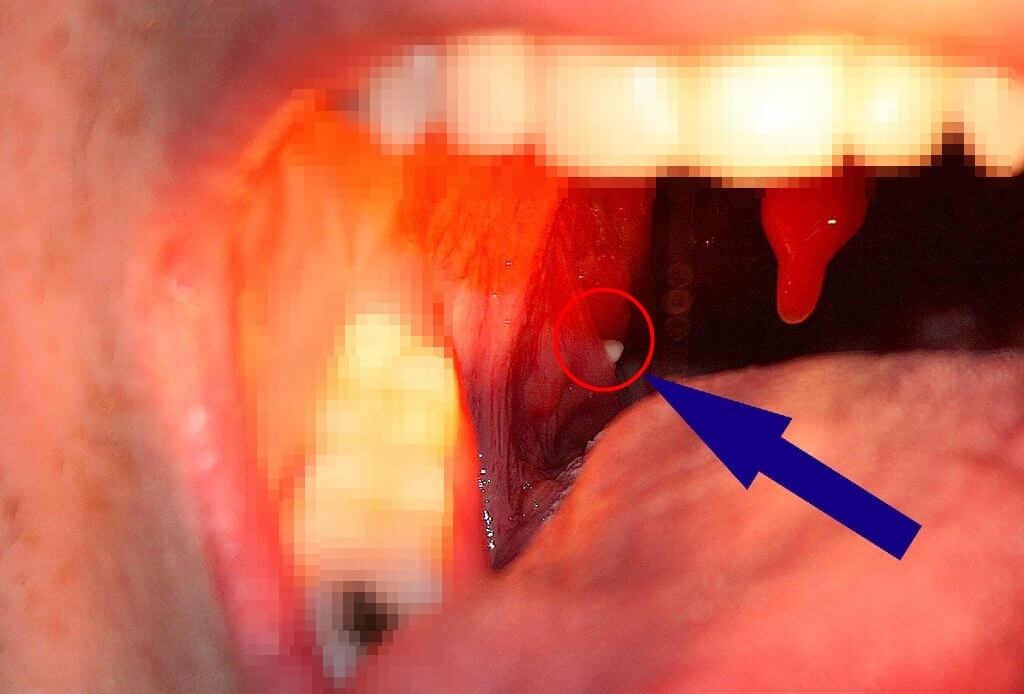

- 편도결석이란?편도결석은 편도선 상에 형성되는 작고 단단한 침전물을 말합니다. 일반적으로 작은 자갈의 크기이지만 아주 작은 것부터 탁구공만큼 큰 것까지 크기가 매우 다양하게 발생합니다. 크기의 다양성 때문에 목에 편도결석이 있음에도 불구하고 잘 느끼지 못하는 경우도 있습니다. 일반적으로 건강상의 문제를 일으킬 만큼 위협적이지 않습니다.

2. 편도결석 원인 편도결석의 원인은 편도선 구조에 있습니다. 편도선은 모양이 주름이 잡혀 있어요. 따라서 이 주름에 우리가 섭취한 음식의 잔여물이나 편도선염을 유발할 수 있는 일부 세균이 끼여 시간이 지나면서 침전되고 석회화된 결석을 만들어냅니다. 이게 편도결석입니다.